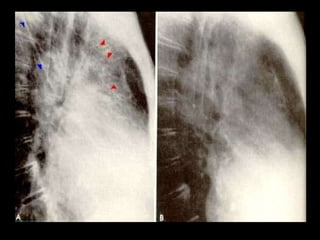

Trama broncovascular normal. Más intensa en las bases.

Trama broncovascular normal.Más intensa en las bases.